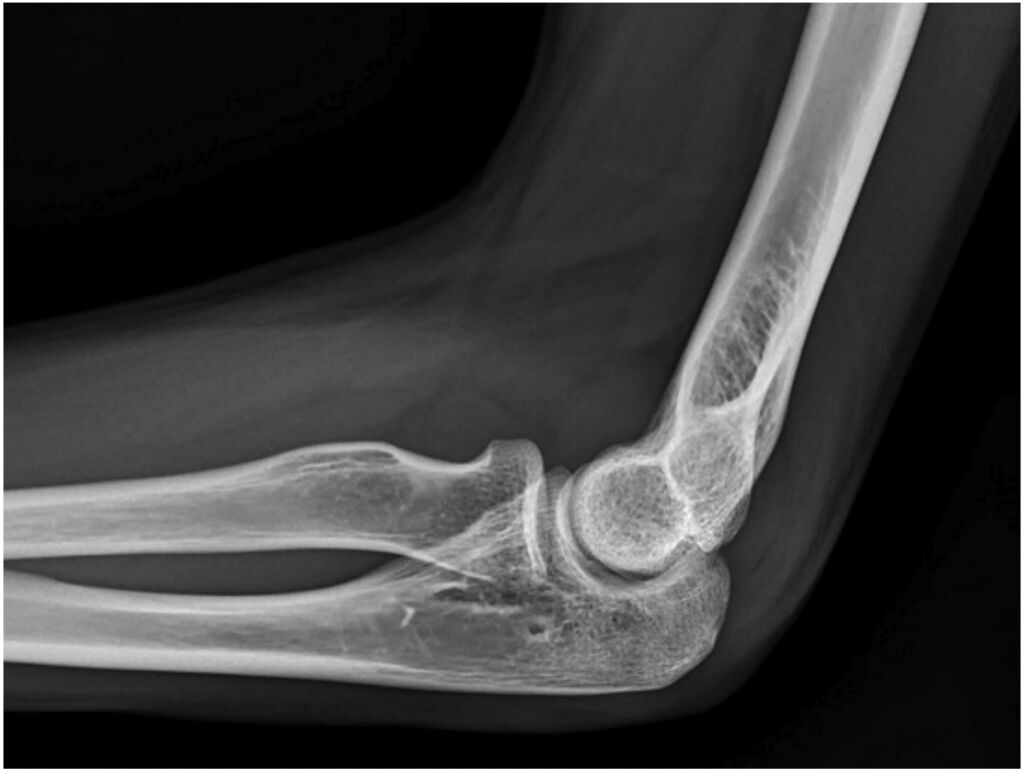

72.病人跌倒後被送到急診室,左手肘劇烈疼痛且無法活動。他的左手肘X光片側面照的影像如圖所示,下列敘述何者最恰當?(A)可明顯發現肱骨(humerus)骨折 (B)可明顯發現橈骨(radius)骨折 (C)生長板(growth plate)尚未癒合 (D)可明顯發現關節積液(joint effusion)